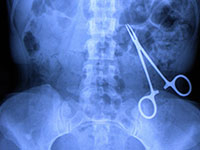

Tous les points de contrôle attendus pour préparer une intervention chirurgicale sont réputés essentiels pour garantir un niveau de sécurité optimal, et ce, quel que soit le secteur d’activités. Dans ce cas clinique, les conséquences de l’utilisation d’un instrument défectueux seront maîtrisées, mais les risques liés à cette vulnérabilité peuvent être potentiellement graves.